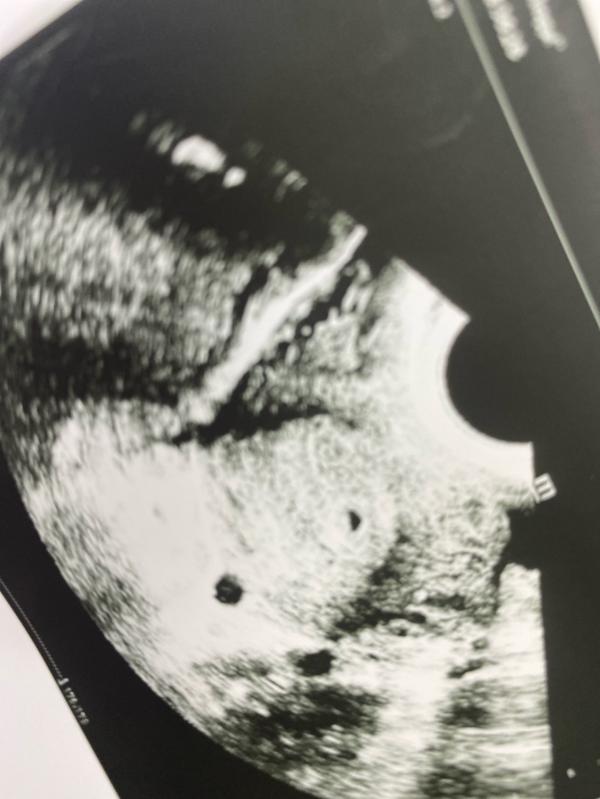

Не смотря на хгч , рано пошла я. Сказали что то в матке есть , может и плодное яйцо . Но типо оно должно быть круглое , у меня не совсем круглое.

Эндометрий 16мм.

Вот сверху фасолька

@ellvii, визуализируется округлое образование неправильной формы 3,5мм вероятно плодное яйцо , вот так написали